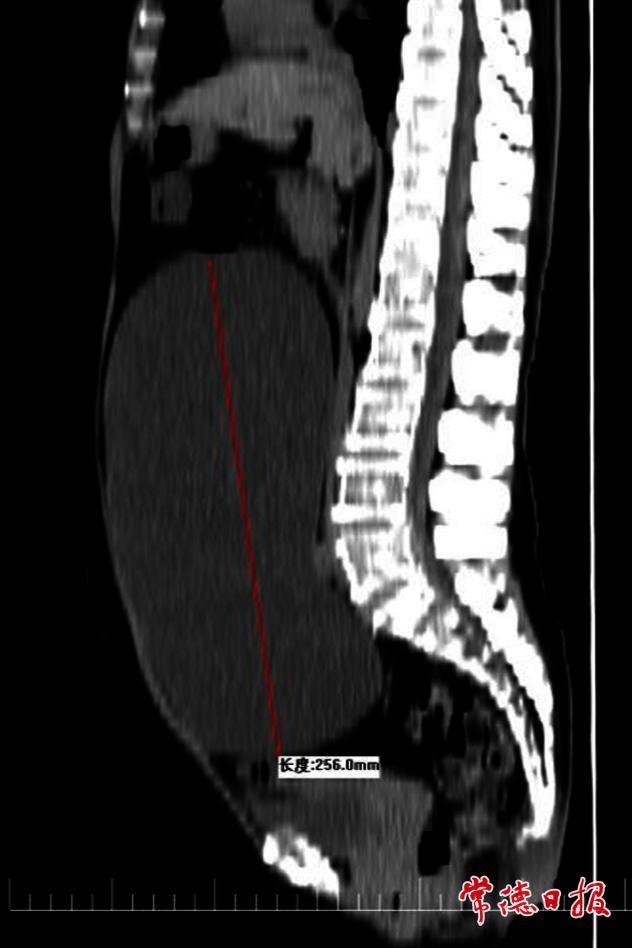

據了解,周女士在兩年前開始察覺腹部逐漸隆起,起初她以為只是年齡增長導致的體重增加,并未在意。然而,隨著時間推移,她的腹部明顯膨隆,周女士這才意識到情況異常,隨即前往醫院就診。經影像學檢查,醫生發現其盆腹腔內存在一個巨大的囊性包塊,來源為卵巢,體積驚人,幾乎占據了整個盆腹腔空間。

面對這一棘手病例,醫院迅速組織多學科聯合會診(MDT)。考慮到患者年齡較大,傳統開腹手術創傷大、恢復慢,可能增加術后并發癥風險,醫療團隊最終決定采用腹腔鏡微創手術方案。該技術僅需開3至4個0.5至1厘米的小切口,既能精準切除囊腫,又能最大限度降低手術對患者身體的傷害。